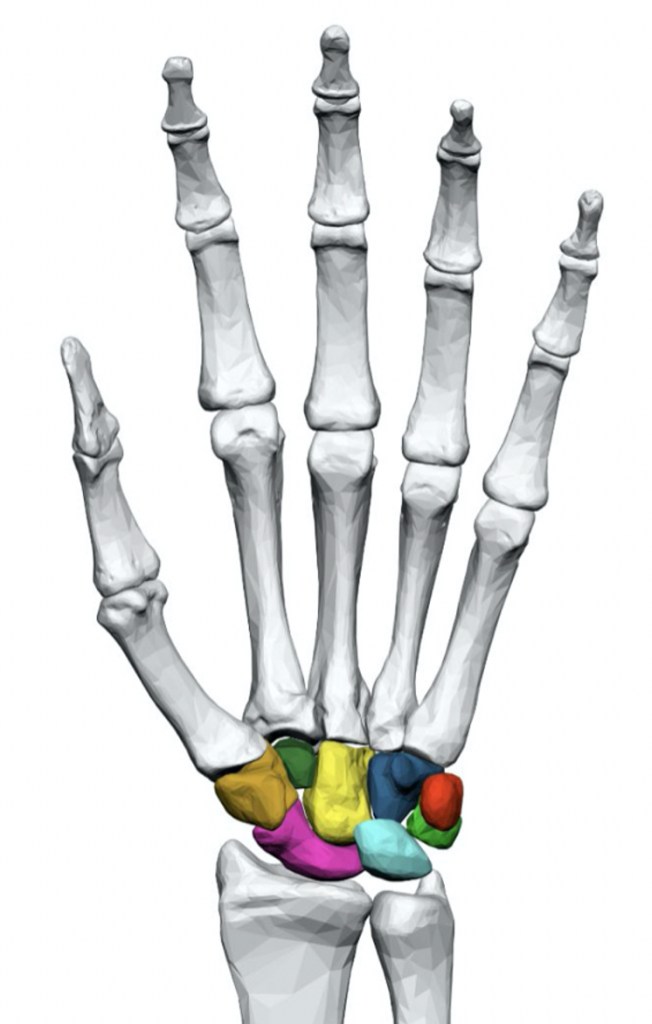

The wrist is the most complex joint in the body. It is made up of eight small bones (carpal bones) and many ligaments, all arranged in a manner to allow a large range of motion.

The most common type of osteoarthritis seen in the wrist joint is a result of the ageing process and genetics. This type of arthritis may target a specific area in the wrist, particularly the joint between the scaphoid, trapezium and trapezoid. Secondary osteoarthritis is more commonly seen following trauma or injury to the wrist, often many years after the initial injury. This initial injury can be a fracture of the radius bone, a fracture of the scaphoid, or an injury to the ligaments between the bones of the wrist.

Proximal row carpectomy: This involves removing the three bones from the wrist (scaphoid, lunate and triquetrum) and permitting the capitate bone to move with the end of the radius bone. Not all degrees of arthritis are suitable for this procedure.